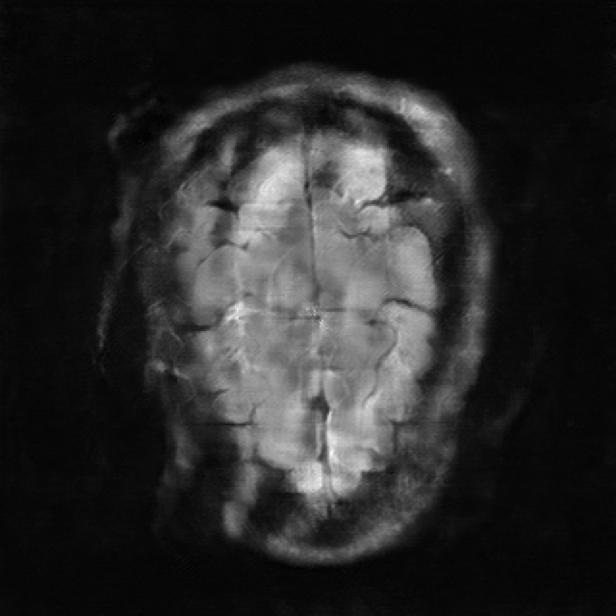

| Ground Truth | E2E-VarNet | UDNO | Nirvana (Ours) |

We also visualize the performance of Nirvana for MRI reconstruction with the undersampling rate set as 8 in Fig. 3. The ground truth, the images reconstructed by E2E-VarNet, UDNO, and Nirvana are shown in the 4 columns, respectively. As shown in Fig. 3, the performance of Nirvana is better than UDNO and E2E-VarNet in terms of the image fidelity and resolution. The reconstructed image of E2E-VarNet is blurry, and some part of the brain is completely obscured by black patches. The reconstructed image of UDNO is roughly close to the ground truth image, but the resolution is low and the details of the image are unclear. However, the reconstructed image of Nirvana is clear and accurate with high resolution, remarkably resembling the ground truth image with the highest SSIM, whose value is 0.8812.